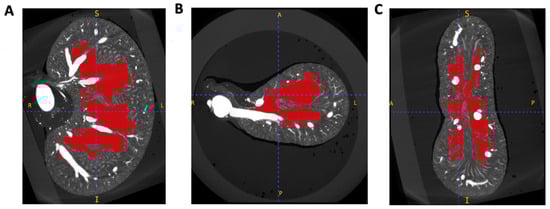

2.2. Image Segmentation and Vascular Density Measurement

3.2. Vascular Modelling of Diabetic Kidney Disease

3.3. Hydronephrosis Prevalence and Severity